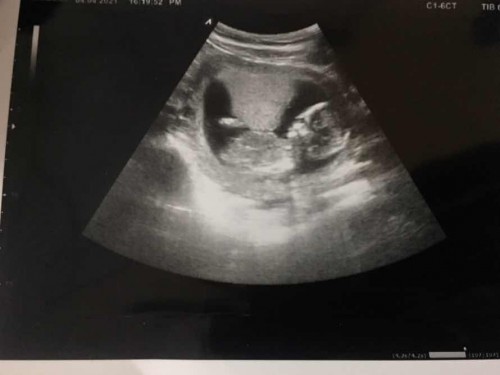

14w3d ค่ะ

ทีมเดือน กันยายน จ้า สถานีต่อไป คัดกรองดาว และ รอลุ้นเพศว่าจะได้ อิปิ๊ หรือ ปิกกาจู๋ 👧🏻👶 #ความสุขของแม่ #ท้องแรก